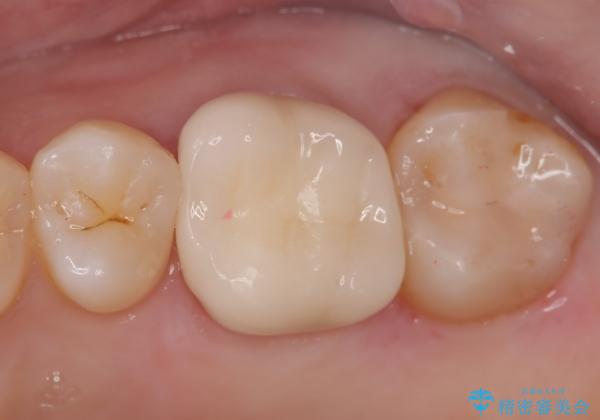

きれいな被せ物になり、患者さんにも満足していただけました。

歯牙の破折を防ぐために、セラミッククラウンにて修復しています。